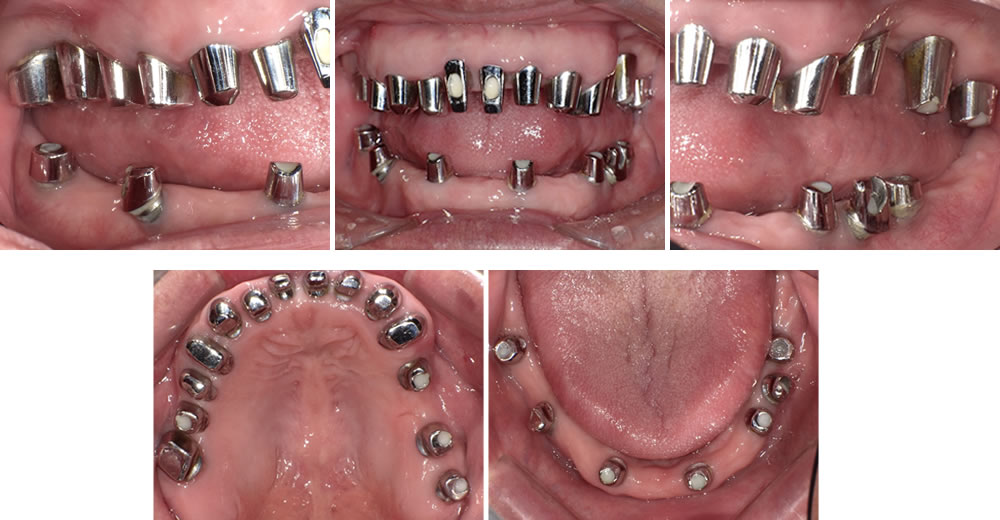

【▼初診時の口腔内】

初診時の口腔内

検査により、歯周ポケット(歯と歯肉の間)が深く、歯肉から出血、歯が動揺して歯周病が進行していたため、まずは歯磨きの仕方や食生活のアンケートを取り、生活習慣を見直ししました。